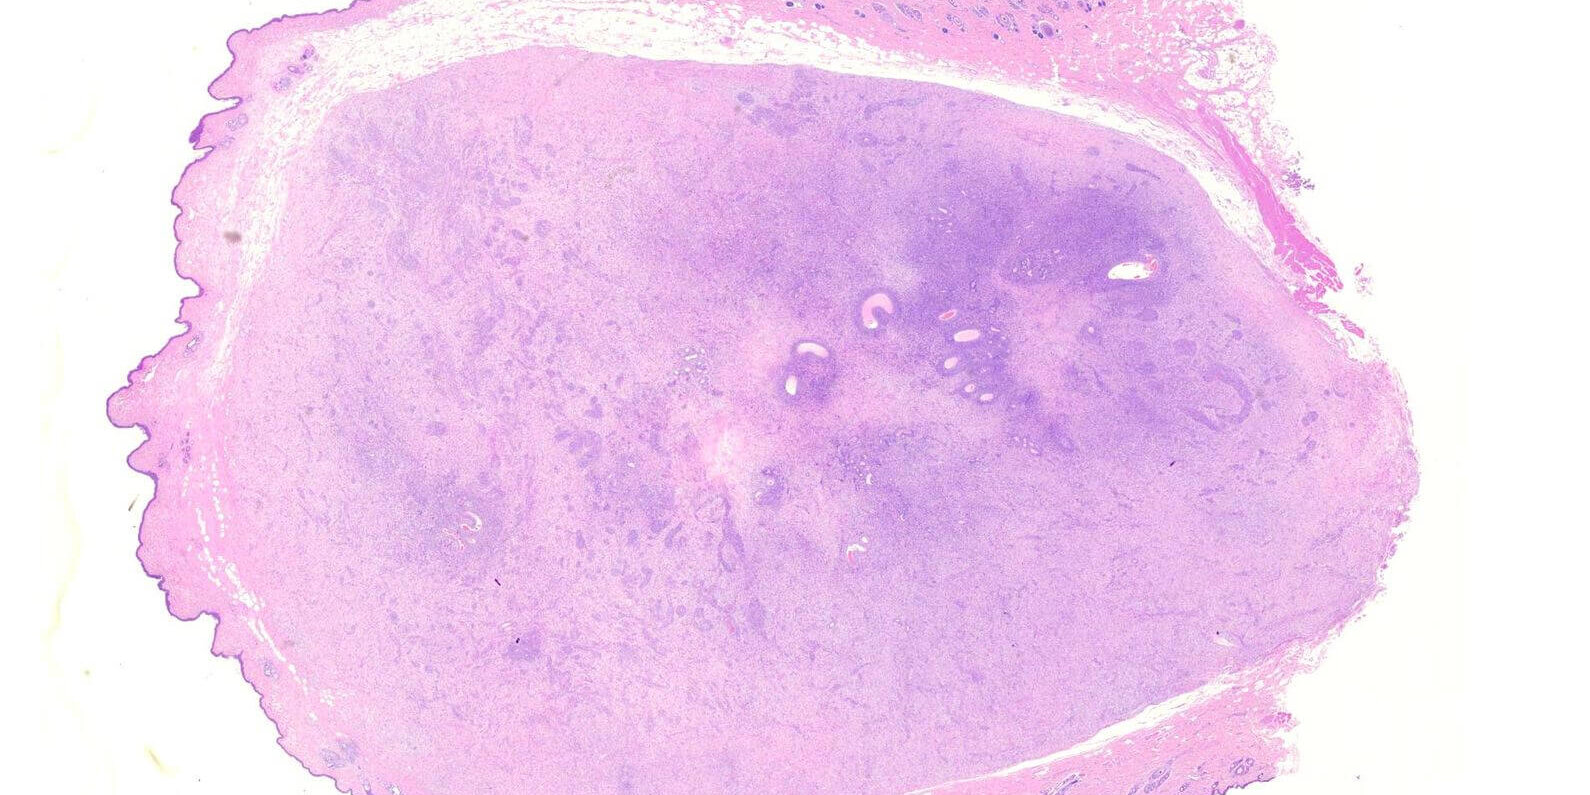

犬貓皮膚常見的一種間葉組織 (mesenchymal origin)來源腫瘤,分類上為軟組織間葉性腫瘤(soft tissue mesenchymal tumors, STMTs)的一種。

此類種瘤的一個特徵,就是在動物四肢或軀幹出現極大型的腫塊,但不一定會有表皮潰瘍。

STMTs腫瘤的組織學惡性程度分級會依據腫瘤細胞的分化程度(differentiation score)、有絲分裂相(mitotic count)、壞色組織面積(necrosis area)進行評分。一般以第2級(grade 2),中度惡性的腫瘤較為常見,具有一定程度的術後復發機率及轉移機率。